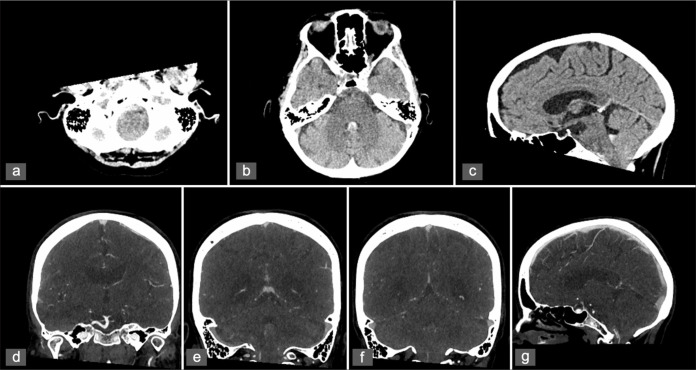

Case description: We present the case of a 77-year-old woman who experienced recurrent episodes of thunderclap headache, which eventually progressed to altered consciousness following admission. Neuroimaging revealed a SAH involving the fourth ventricle and basal cisterns, alongside cerebellar tonsillar herniation and obstructive hydrocephalus, with no arterial source identified on serial angiography. Magnetic resonance imaging confirmed CM1, with tonsillar descent to the C1 level. The patient underwent suboccipital decompression for refractory intracranial hypertension that prevented weaning from the external ventricular drain. Intraoperative exploration revealed an abnormal posterior spinal vein traversing the arachnoid membrane, which was suspected to be the source of the hemorrhage and was successfully coagulated.